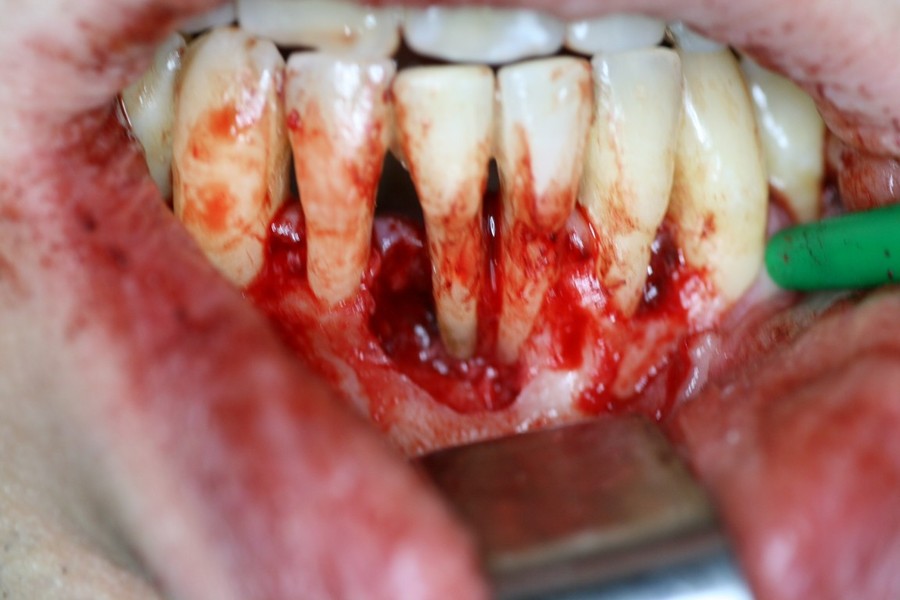

Rigenerazione Gravi difetti parodontali

Rigenerazione difetto parodontale di un canino inferiore con materiale eterologo